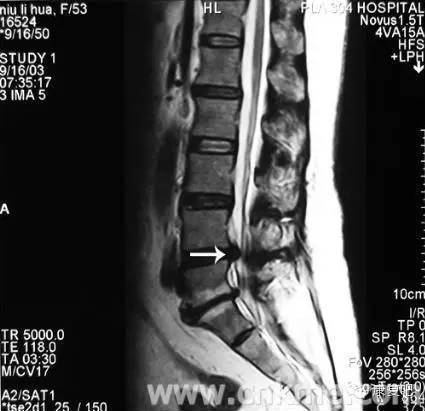

3、核磁共振攝影(MRI)

可顯示出狹窄的部位(脊髓腔的狹窄)、椎間盤物質的突出進入脊髓腔、或受侵害之脊髓神經根。